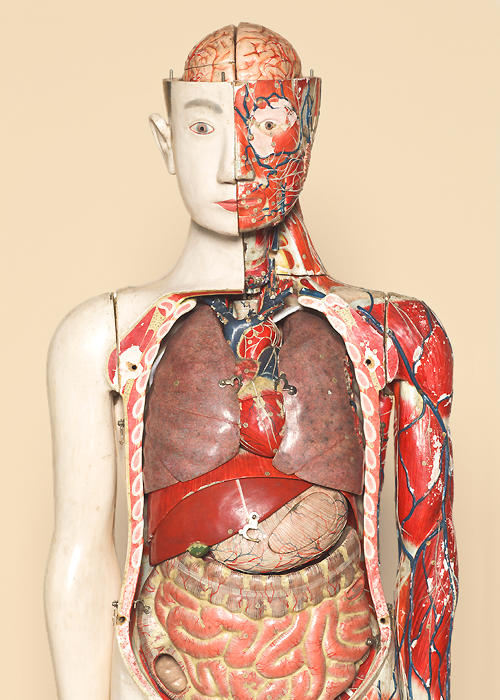

"Human anatomical models/specimens"

Conventional anatomical models were heavy as they consisted of plaster coated with lacquer. They have been replaced with paper-made with resign coating which became known as the Shimadzu fiber manufacturing technique.

Shimadzu fiber was light, carried colors well, and was resistant to water. The manufacturing technique was granted a patent.

Finally, they were able to announce a human anatomical figure that could be broken down into 138 parts.

For children, this was the first time that they saw the structure of human body. It should have been the "mystery of life."